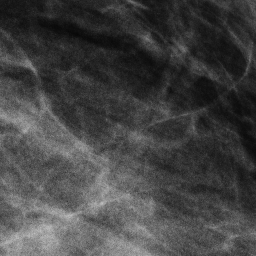

3.3 Anomaly Segmentation

Generative models are often used within an anomaly segmentation pipeline [45, 43, 2]. This enables the model to make pixel-wise predictions on lesion presence, while not requiring pixel-wise annotations for training. Therefore, the proposed models’ effectiveness is evaluated for this downstream task. To do so, the whole image model is used, trained only on healthy images without any lesions, therefore capturing the distribution of images of breasts that consist entirely of healthy tissue. A limited amount of Gaussian noise is added to the diseased images, which are then denoised using the proposed model. As it is capable of generating only healthy tissue, the lesions from the image are not reconstructed, and the surrounding healthy tissue is well-replicated. By comparing the original mammogram with the denoised version, the map of anomalies present in the image is obtained.

Noise is added for steps, using the forward noising procedure used in DDPM, where . is a hyperparameter that determines the start point of denoising, balancing original information preservation (lower ) and anomaly removal (higher ). In the latter case, the difference of non-anomalous parts might be too big, and even the breast shape and tissue density might change.

To automatically compare the most important regions of the image, a binary segmentation mask is first needed that precisely outlines the breast area and distinguishes it from the surrounding background.

We can use the breast mask derived from the original image to extract the region of interest in both the original and the denoised image. We then perform histogram matching on these two images, as this accounts for all the changes that the diffusion process introduces in the overall pixel intensities, which could adversely influence the anomaly segmentation process and create spurious differences.

Once this is done, the initial anomaly map is created by subtracting the denoised image from the original. As the breast cancer, including masses, appears white in mammograms [27], this anomaly map is expected to contain more positive than negative values in the anomalous regions on average. Therefore, all negative values are set to zero. This could analogously be used in detecting dark lesions (e.g. some types of cysts) by inverting the values in the image.

Finally, changes that are less than of the intensity of the pixel with the highest intensity are discarded. This step is performed to remove all the non-significant high-frequency changes introduced by the diffusion process. On top of this, a Gaussian blur is applied to further smooth the high-frequency noise and get the final anomaly map.

4.6 Anomaly Segmentation

The InBreast dataset was used to evaluate the anomaly segmentation performance. The evaluation scenario is basically zero-shot, as the images tested on are different from those used to train MAMBO on. To allow comparison with existing approaches used in the domain of radiology, only the low-resolution (global context) model was used as described in Sec. 3 and trained on the subset of healthy images taken from the VinDr dataset.

To select the optimal value of the timestep parameter () for the anomaly segmentation task, values in the range were evaluated. The optimal value of , was obtained for all masses in the dataset, corresponding to an IoU of 0.216.

To further probe the capabilities of recognizing lesions of different sizes, Tab. 6 illustrates the performance of MAMBO using the optimal . To produce the data, lesions are grouped in buckets according to size. The size of lesions (in pixels) in the dataset follows an exponential distribution. Lesions are assigned to the buckets using a logarithmic scale, which yields buckets with the same number of images (18) in each, except for the last bucket, which contains 17 images.

As Tab. 6 shows, larger lesions are easier to detect using the model. Exceptions occur when a lesion grows large, nearing breast size, and the model finds it difficult to remove the whole anomaly. Quantitatively, the best result achieved by the proposed approach is as high as , a significant improvement over the reported for AnoDDPM in [44] for brain radiology images.

12 Additional Results for Anomaly Segmentation on the InBreast Dataset

Tab. 9 shows the IoU score for the anomaly segmentation sub-task as a function of the number of timesteps used to add noise to the image. For values less than 600, model performance in terms of the IoU score is low. This could mean that the level of noise, for those values of , is still too low to cover the target anomaly completely.

Figure 10 shows additional results of anomaly segmentation on the InBreast dataset, using the MAMBO low-resolution (global-context) model, for the size of lesion that the approach detects well, as well as one which is challenging for it.